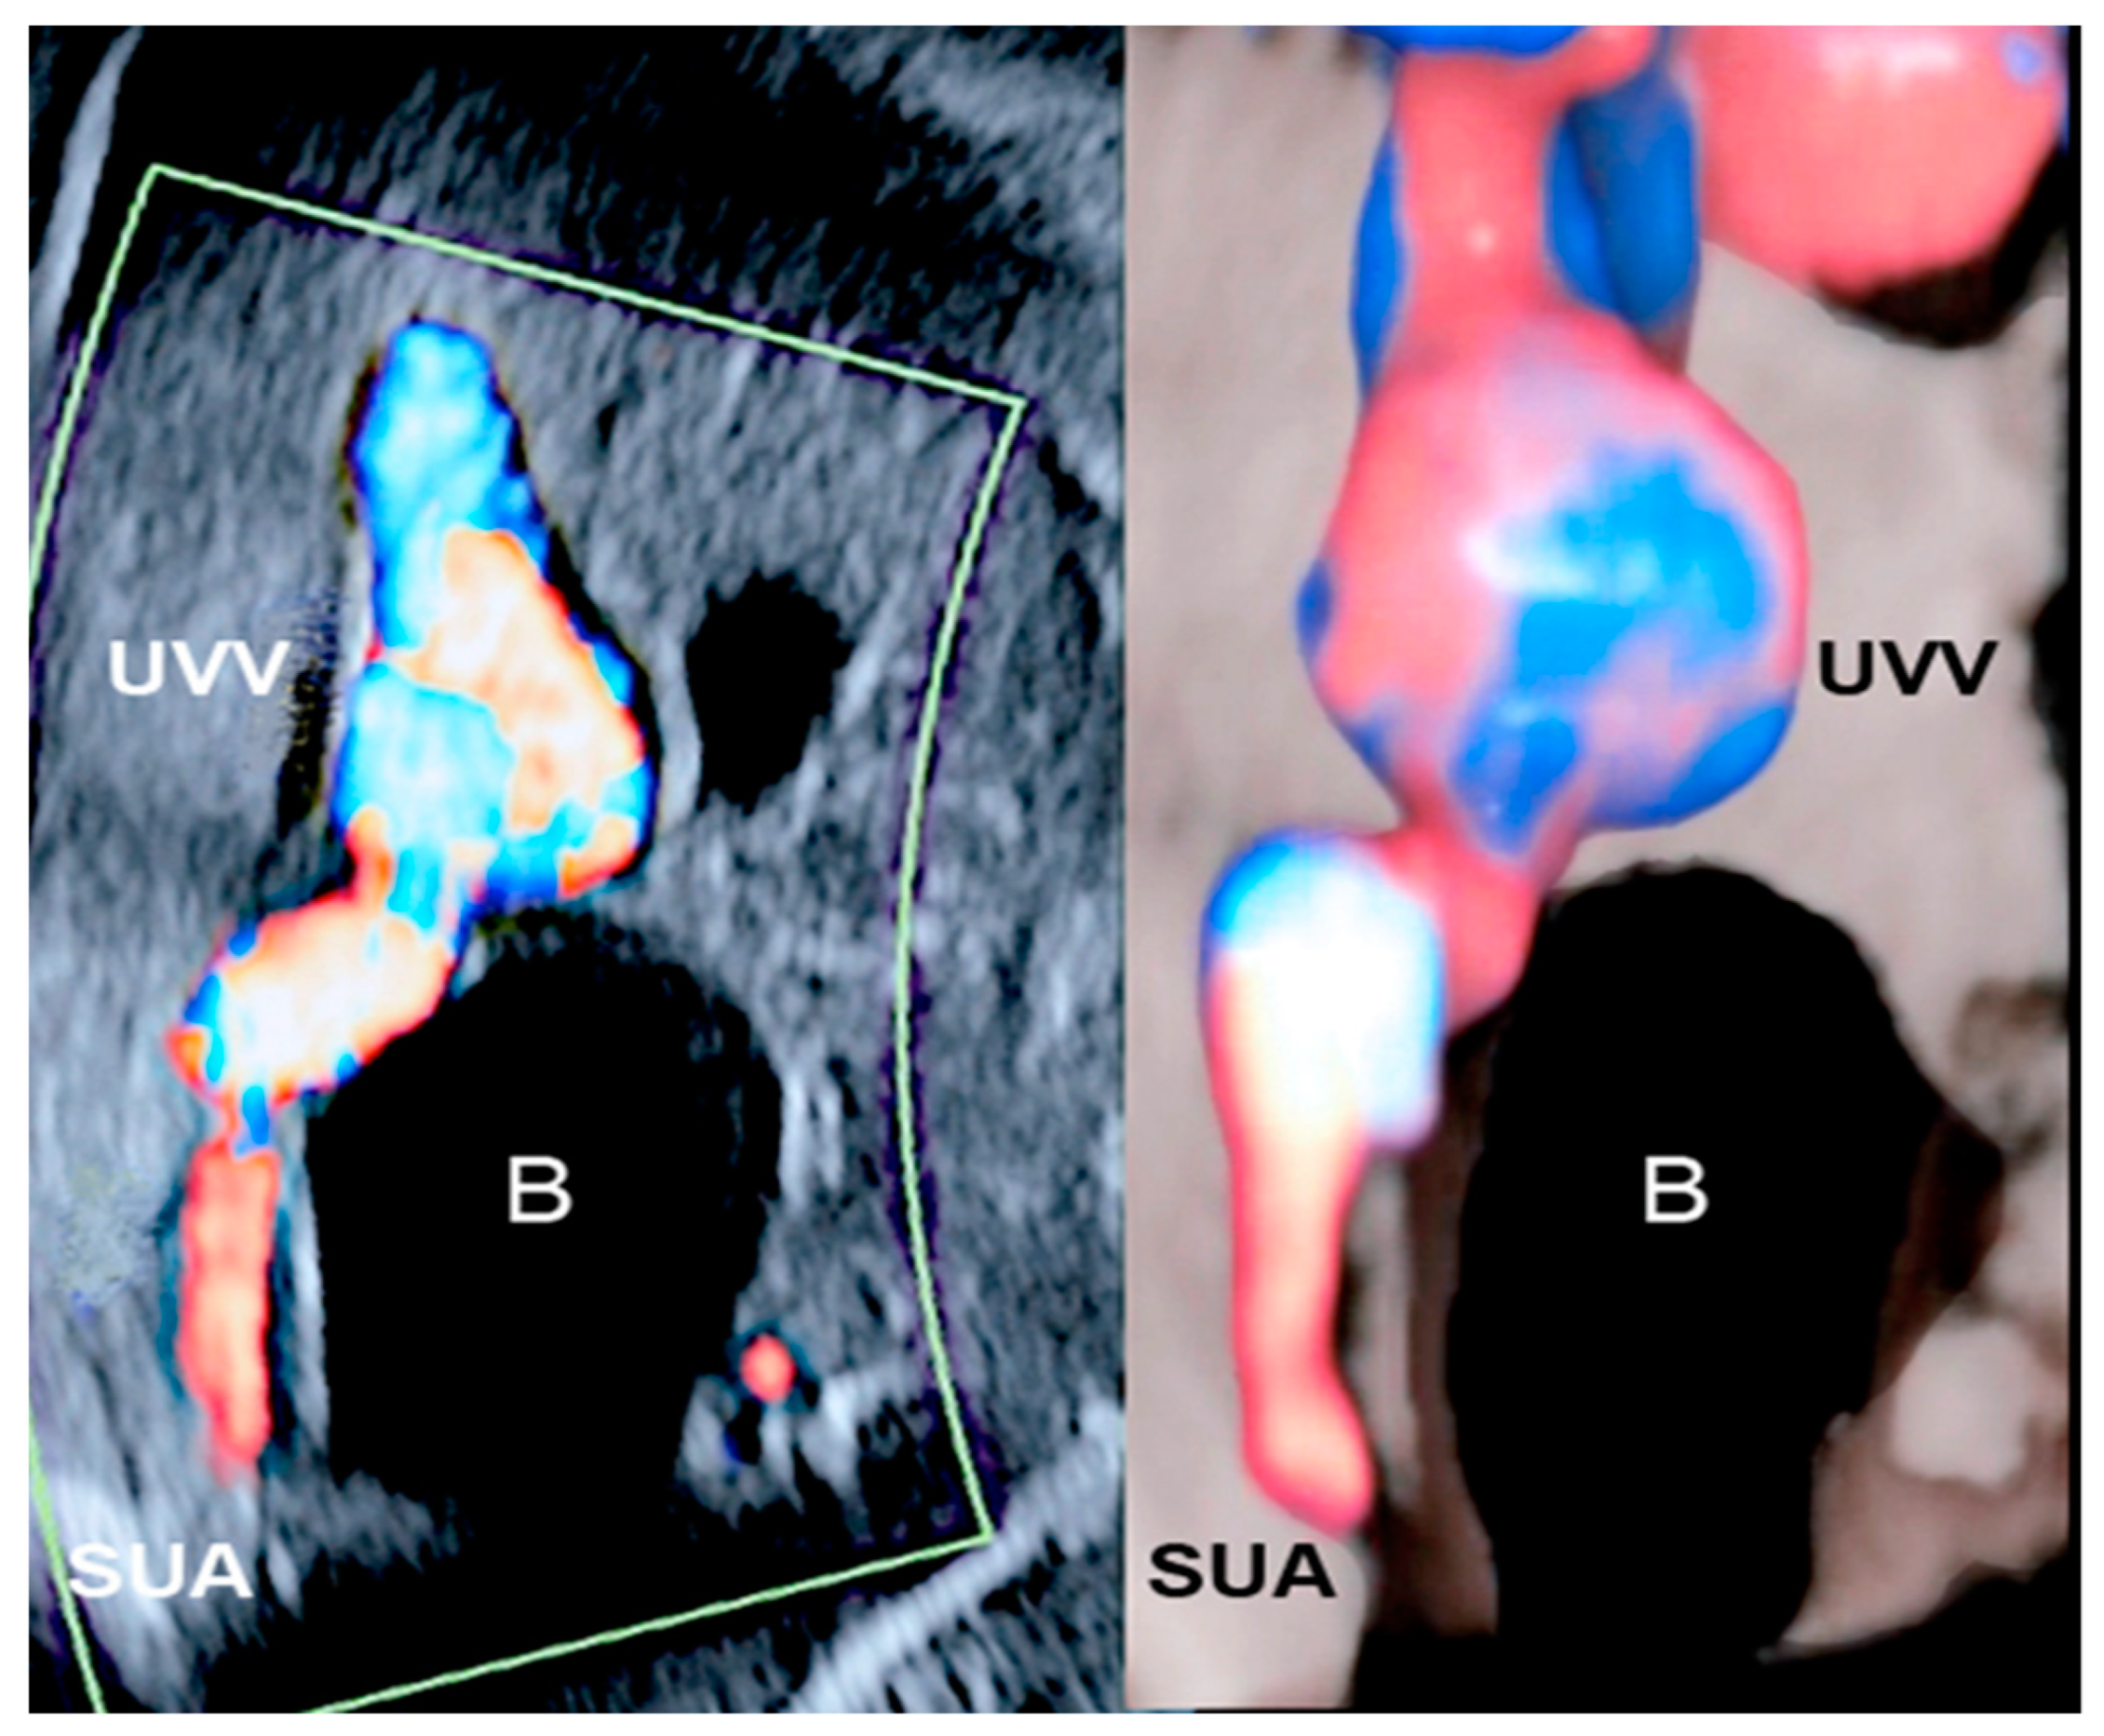

3.4. Single Umbilical Artery